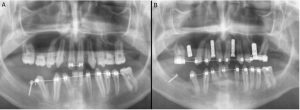

No obstante, la mejor forma de averiguar si se trata de agenesia o no, es mediante una radiografía de la boca, en la cual veremos si realmente hay diente y no puede salir por algún motivo o, por el contrario, no existe.

Para confirmar esta sospecha inicial debe realizarse un escáner o radiografía que proporcione al especialista una visión completa de lo que sucede en el interior.